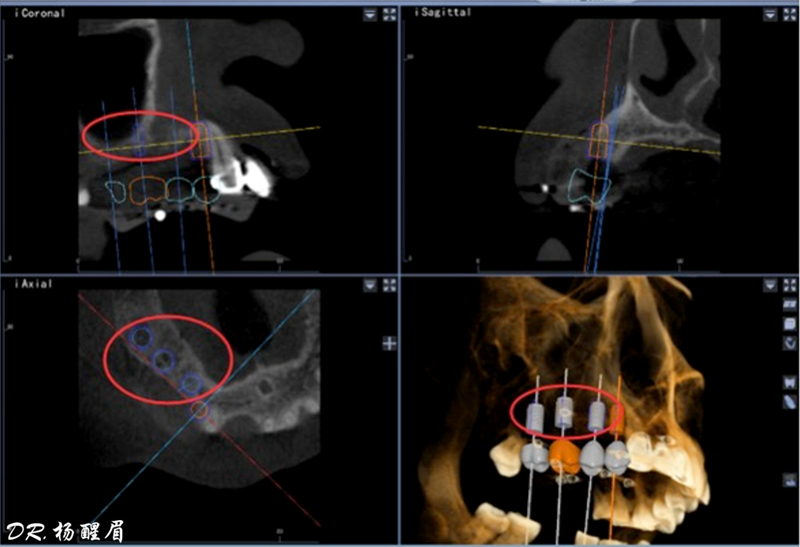

多牙位種植對(duì)于醫(yī)生來(lái)講,手術(shù)難度高。不僅要保證相鄰植體間的位置關(guān)系,還要考慮咬合關(guān)系,也要在術(shù)中根據(jù)患者實(shí)際翻瓣情況隨時(shí)調(diào)整手術(shù)方案。今天,就給大家分享一場(chǎng)由華西口腔醫(yī)院楊醒眉教授主刀的精彩的后牙多牙位種植...

此病例中主刀醫(yī)生借助迪凱爾數(shù)字化口腔種植手術(shù)導(dǎo)航系統(tǒng),精確的控制每鉆的定點(diǎn)精度和角度,保證了每次制備定點(diǎn)誤差小于0.4mm,角度偏差不大于3.5°,極大的保證了種植體按照種植前的手術(shù)設(shè)計(jì)就位。